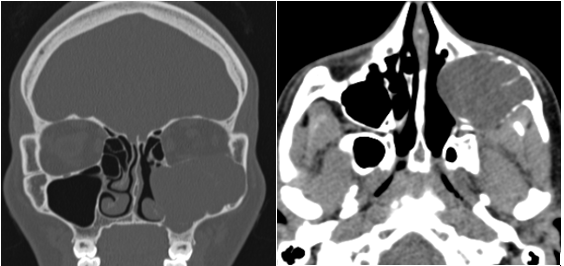

The left maxillary sinus was hypoplastic and it was observed that the floor of the left orbit was lowered into the sinus (Figure 4).

Figure 4 Computed Tomography.

A-Coronal CT: an expansive lesion in the right maxillary and ethmoid sinus that displaced the nasal septum, and a descent of the left orbital floor is observed, B- Axial CT: a collapse of the left maxillary sinus walls is observed.

The MRI revealed a right expansive lesion with variable signal, predominantly hypointense on T2 and hyperintense on T1, the left maxillary sinus was hypoplastic and the floor of the eye descended into the sinus (Figure 5 ).

Figure 5 MRI.

A lesion with variable signal is observed, which occupies the right sinus cavities, displaces the nasal septum and compresses the contralateral intersinus nasal wall causing a left maxillary sinusopathy, collapse of the sinus walls and descent of the orbital floor (the dotted line indicates the level of both orbital floors).The presumptive diagnosis was allergic fungal sinusitis.